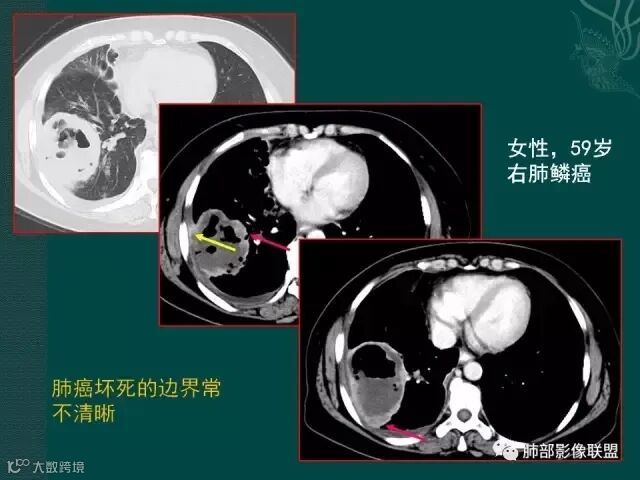

大片液化坏死,内多发空泡,初学者可能感觉是感染,但红箭头所指洞壁虽然不很厚,但仍可见到边界不清的低密度区,黄箭头所指病变侵犯胸膜。

鳞癌破坏力在所有类型肺癌中,都是最强的,所以出现坏死的几率特别是大片坏死的概率,是远远高于腺癌。

厚壁,大部分坏死,外缘较清晰,穿刺时千万不要穿坏死区;